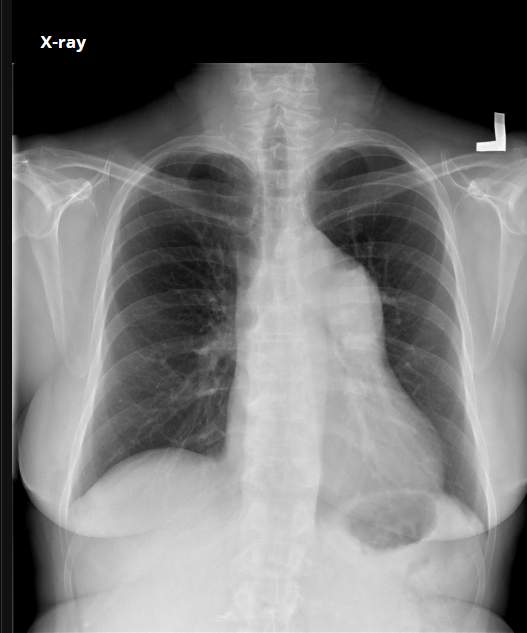

RN a termo.

Cardiomegalia massiva em um neonato com pulmão normal (sem edema alveolar ou intersticial, sem derrame pleural)

Cardiomiopatia neonatal.